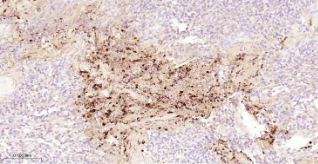

Immunohistochemical analysis of paraffin embedded Human tonsil tissue slide using IHC0669H (Human IL-8 Kit).